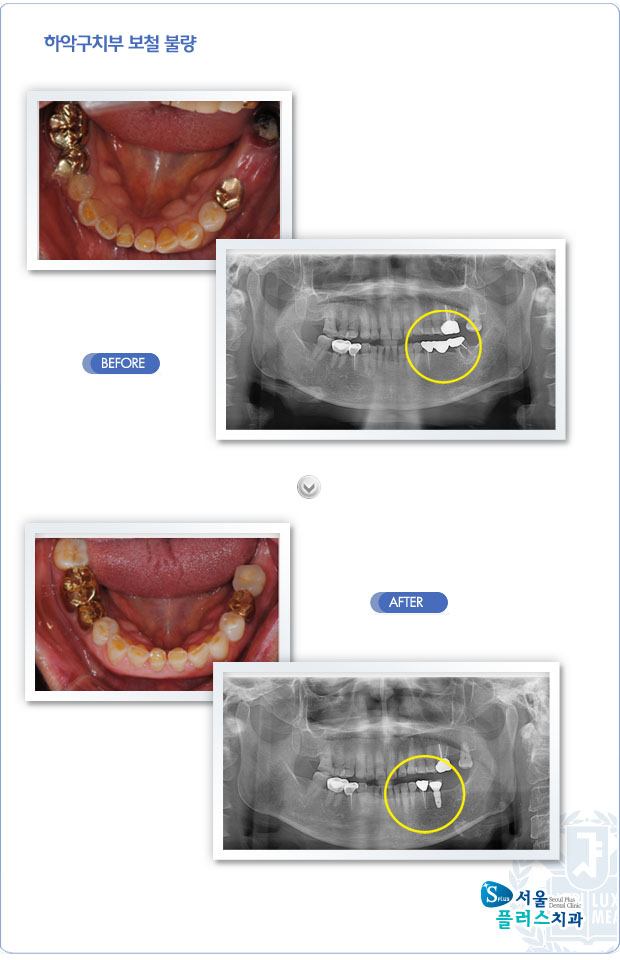

[임플란트] 하악구치부 보철 불량